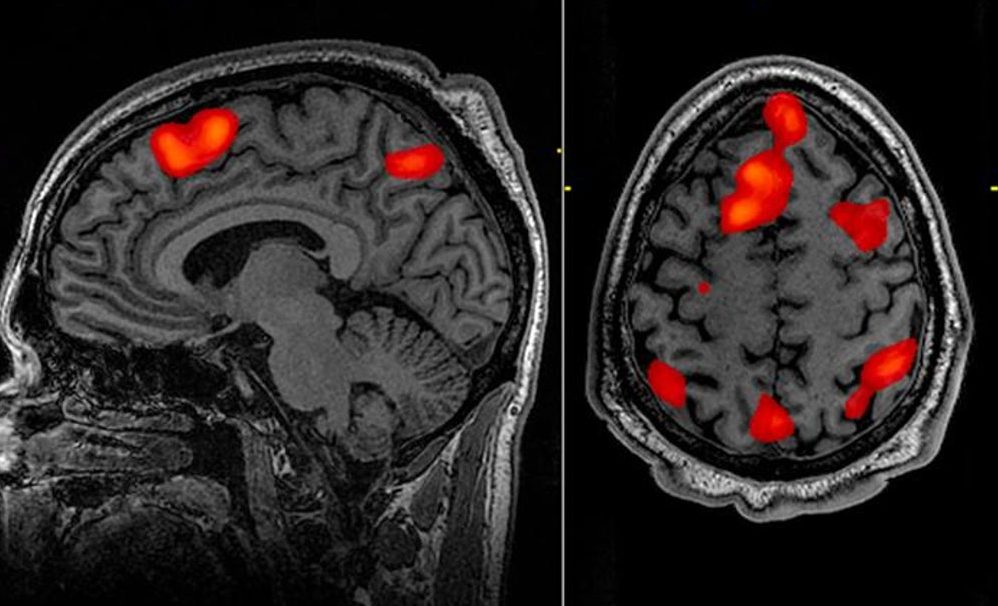

Voltar Estudo indica que lembranças da vida passam mesmo “diante dos olhos” na hora da morte

Enquanto um grupo de neurocientistas avaliava um paciente de 87 anos com epilepsia, o idoso acabou sofrendo um ataque cardíaco e morreu. Diante do resultado inesperado, foram obtidos dados inéditos de como o cérebro se comporta na hora da morte, e o que impressionou os pesquisadores foi a indicação de que lembranças da vida são resgatadas nos últimos momentos de vida. Tal percepção foi revelada por padrões de ondas rítmicas semelhantes às que são registradas durante o sono ou a meditação.

A ondas cerebrais do tipo gama mencionadas por Zemmar são referentes a funções altamente cognitivas, relacionadas à concentração, sonhos, meditação, recuperação de memória e processamento de informações. Por isso, o cientista avalia que o cérebro pode reproduzir uma última lembrança de eventos importantes da vida pouco antes da morte através da geração de tais oscilações.